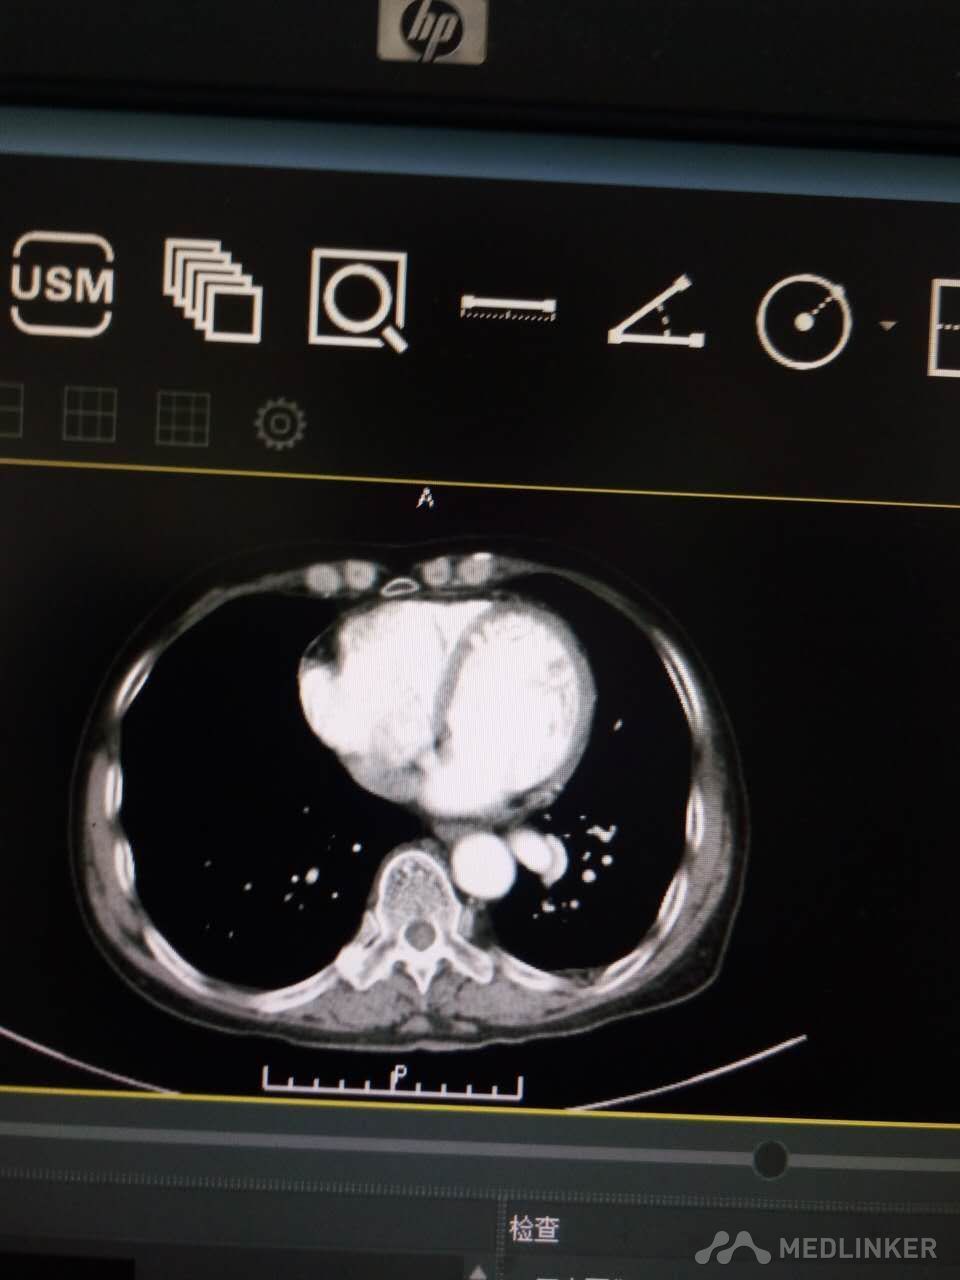

肺血管畸形一例

血管痉挛